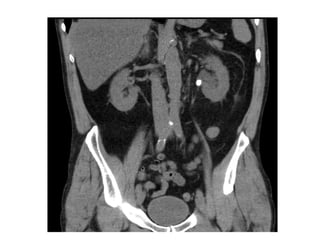

:  www.myoquip.com.au/HipneeFlex.htm 1, Rectus abdominis muscle. 2, Colon 3, Liver. 4, Right kidney. 5, Inferior vena cava. 6, Psoas muscle. 7, Aorta. 8, Lower pole of the left kidney. 9, Left colon. 10, External oblique muscle. 11, Internal oblique muscle. 12, Transversus abdominis muscle.  www.info-radiologie.ch/abdominal_ct.php radgame.stanford.edu/.../Xray/pages/Xray-1.htm

: www.myoquip.com.au/HipneeFlex.htm1, Rectus abdominis muscle. 2, Colon 3, Liver. 4, Right kidney. 5, Inferior vena cava. 6, Psoas muscle. 7, Aorta. 8, Lower pole of the left kidney. 9, Left colon. 10, External oblique muscle. 11, Internal oblique muscle. 12, Transversus abdominis muscle. www.info-radiologie.ch/abdominal_ct.php radgame.stanford.edu/.../Xray/pages/Xray-1.htm